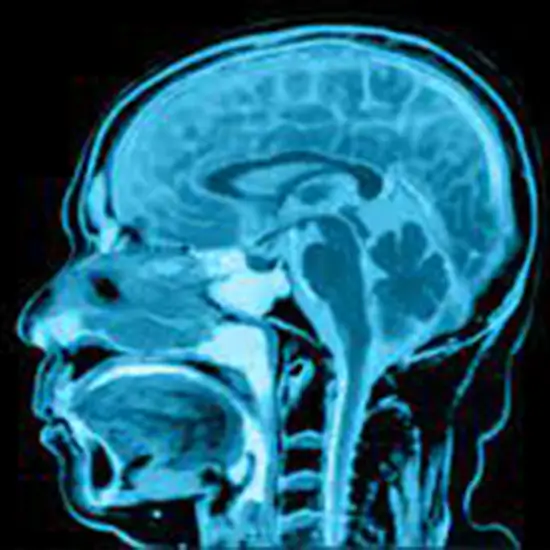

What is MRI Head Screening?

An MRI of the head uses strong magnets and radio waves to take pictures of the brain and nerve tissues around it.

MRI (Magnetic Resonance Imaging) Head Screening is a non-invasive medical diagnostic tool used to obtain detailed images of the head. MRI Head Screening is used to show abnormalities in the head like stroke, injury, fracture, trauma, infection,  masses etc.